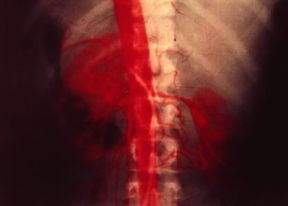

aortografìa

sf. [da aorta+-grafia]. Visualizzazione radiografica dell'arteria aorta, ottenuta mediante l'introduzione in essa di un mezzo di contrasto ad alto tenore iodico per puntura diretta del vaso (aortografia translombare), per cateterismo arterioso (aortografia transradiale o transfemorale) o per via venosa, nella vena del gomito di uno o di ambedue gli arti. L'aortografia pone in evidenza tutti gli aspetti del circolo in esame con i particolari morfologici e funzionali mostrando la sede e il decorso dell'arteria, le condizioni delle sue pareti e la presenza di eventuali obliterazioni.